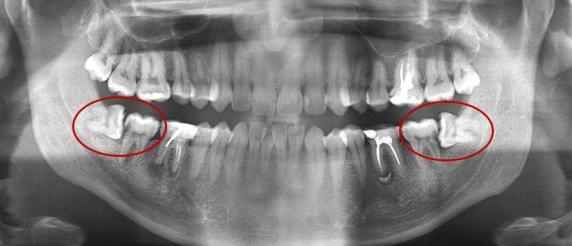

Es una especialidad encargada de la rehabilitación de las alteraciones en la parte de la cabeza y el cuello, incluyendo la boca y los dientes, a través de un diagnóstico y un procedimiento quirúrgico para corregir estas anomalías, como tumores, problemas estéticos, muelas del juicio, entre otros.